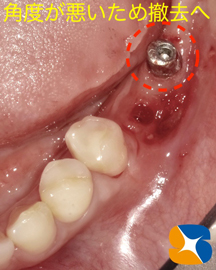

残された奥のインプラントも方向(角度)が悪いため操作性が良くありません。新しく移植するインプラントとも相性が悪いため、ためらうことなく撤去いたしました。(※事前に説明済み)

簡単に抜け落ちたインプラント跡と残されたインプラント